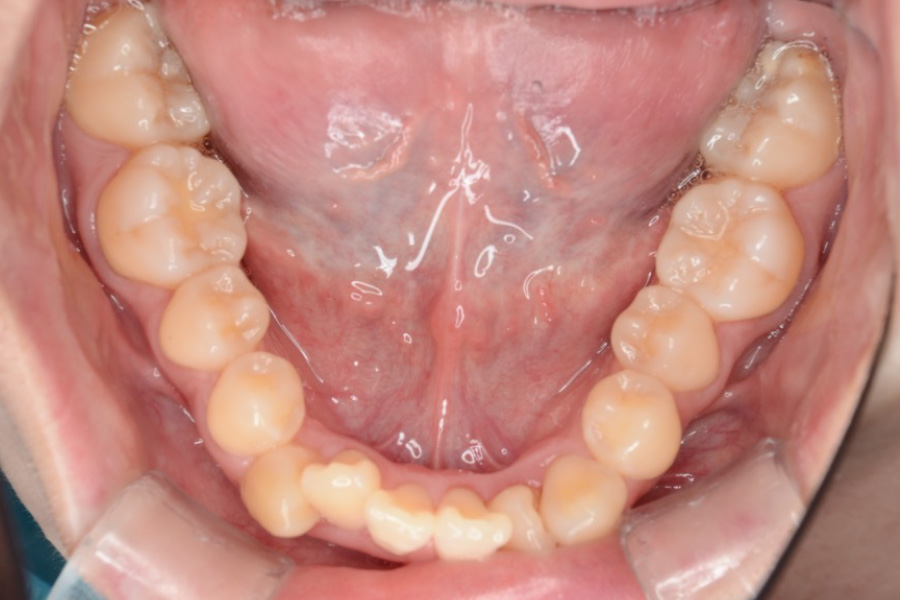

治療前

主訴 全体のガタつきが気になる

期間 2年

費用 220,000円〜660,000円

治療内容 インザライン矯正

小臼歯抜歯